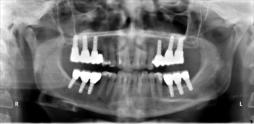

Beispiele für komplexe implantologische Versorgungen aus unserer Gemeinschaftspraxis

(Planung / Endversorgung -- als Röntgenaufnahmen)